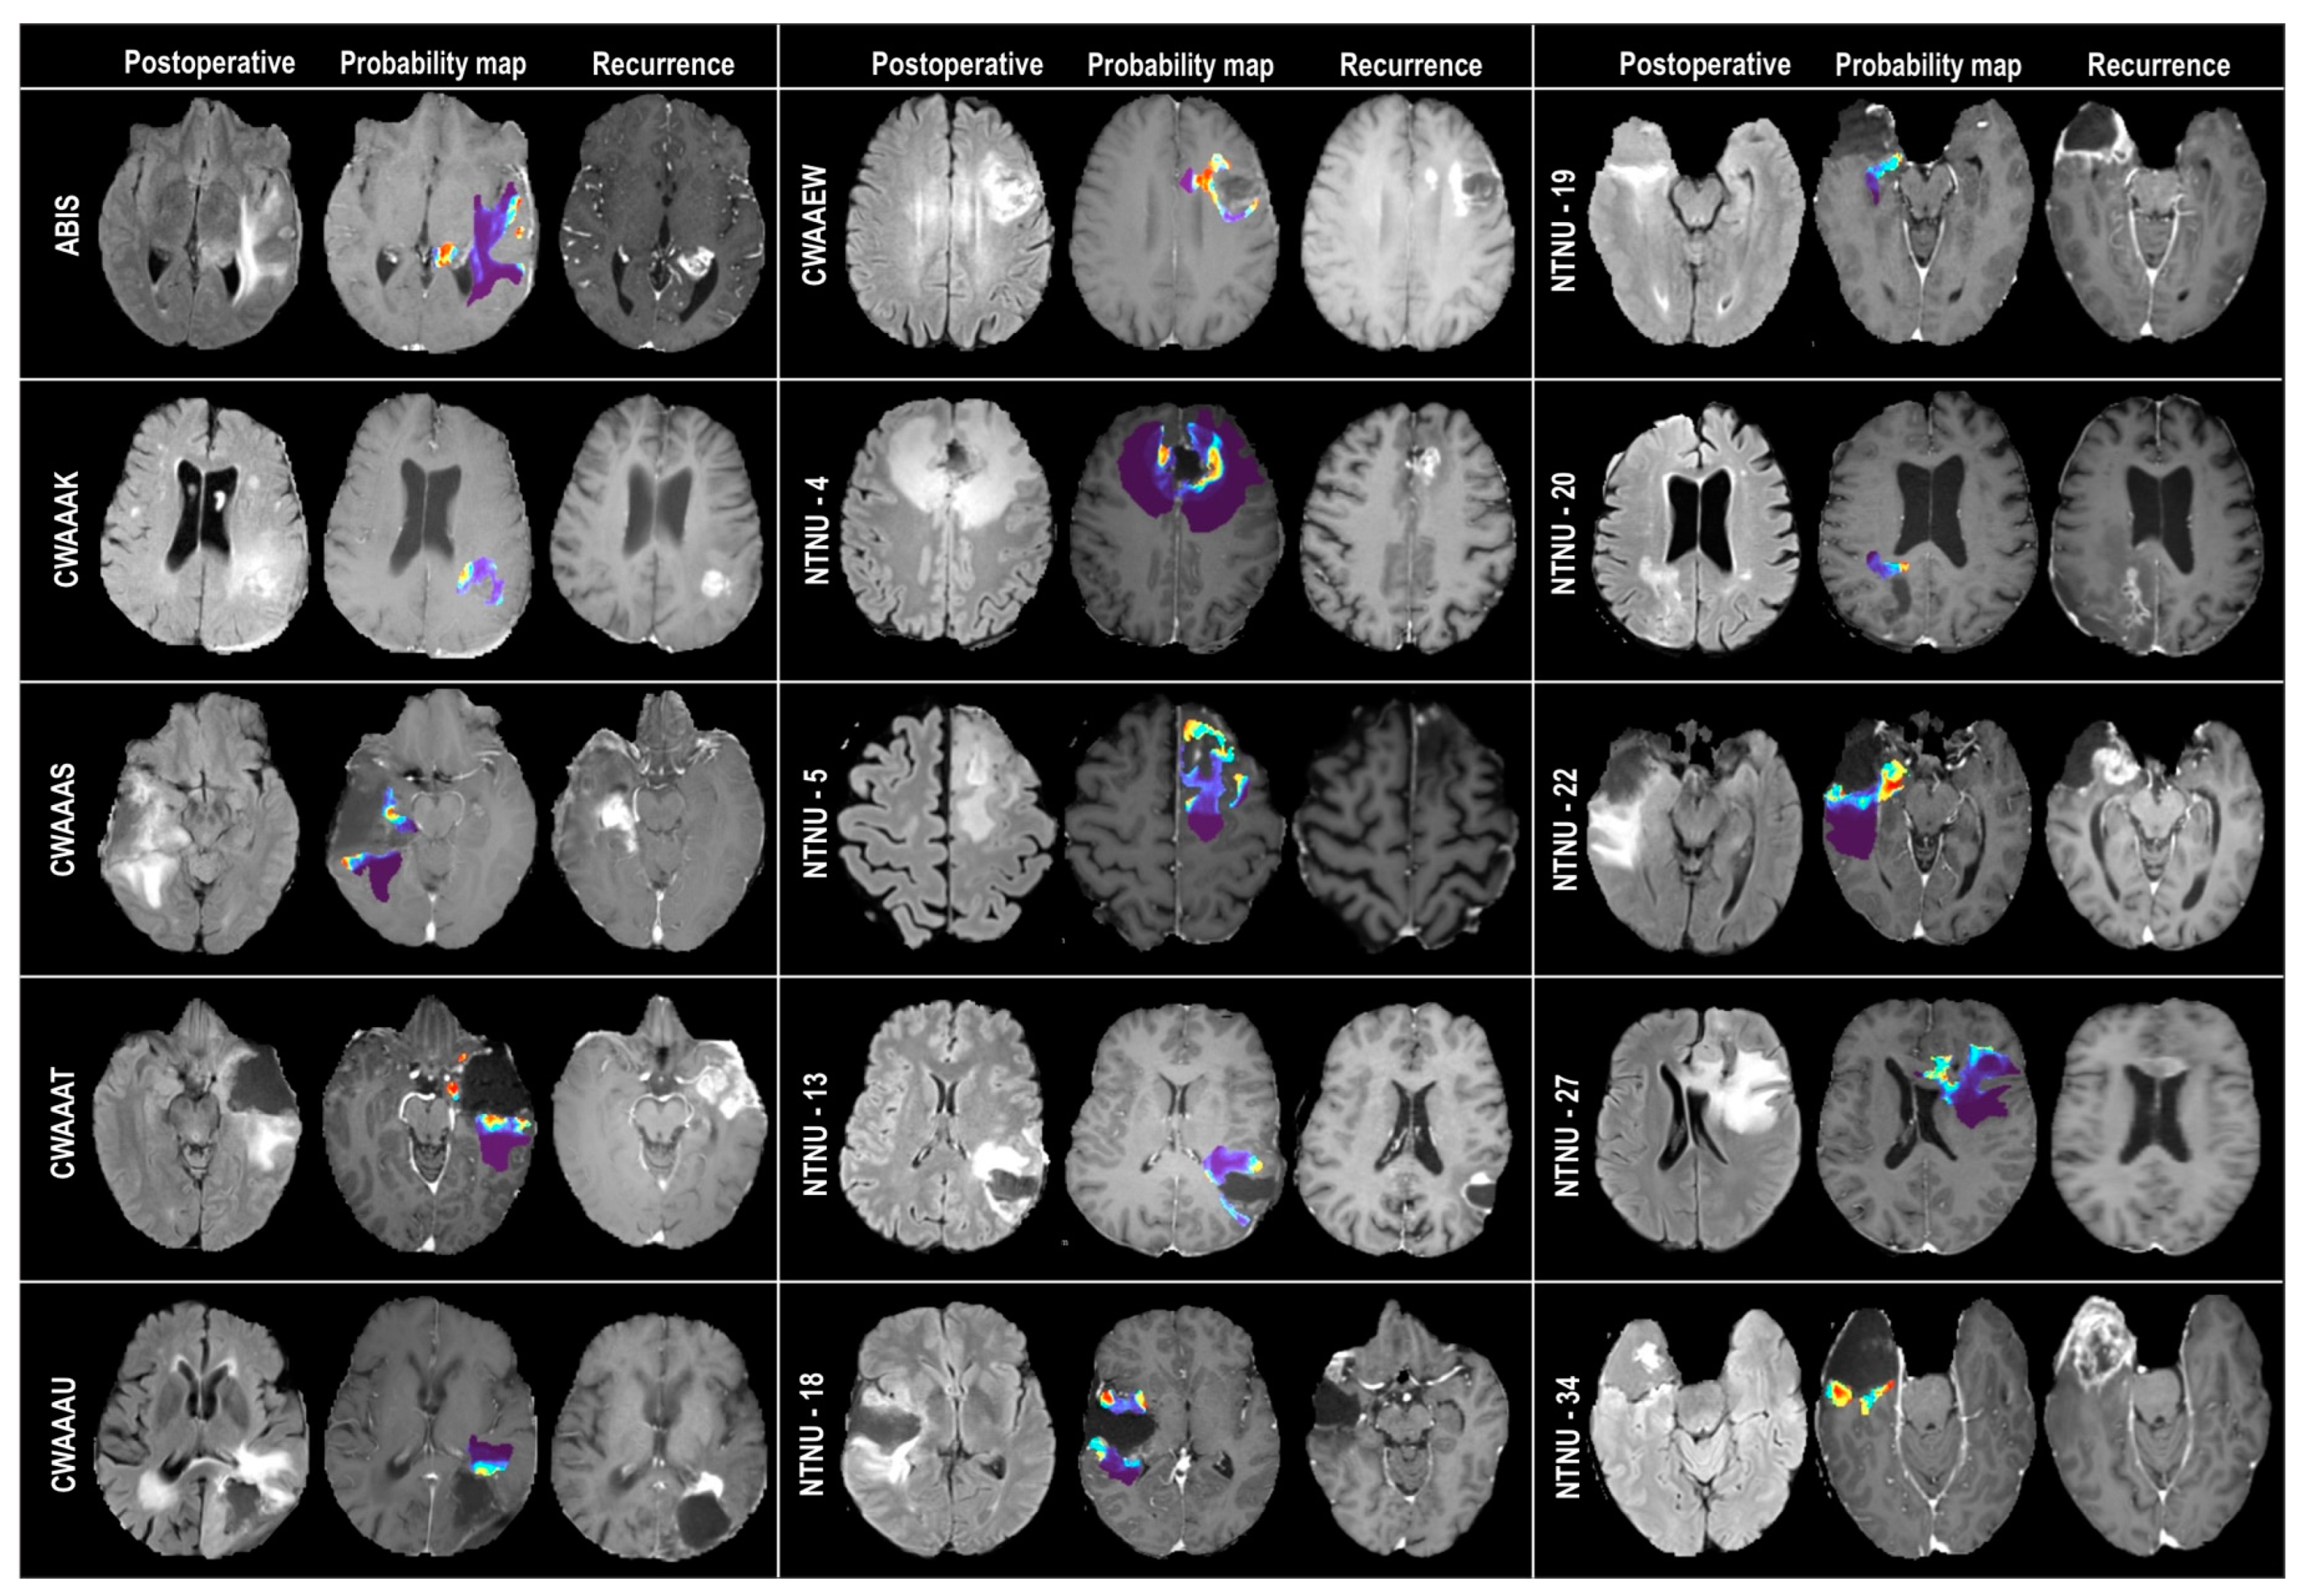

2.6. Probability Maps and Predicted Recurrence Labels

3. Results